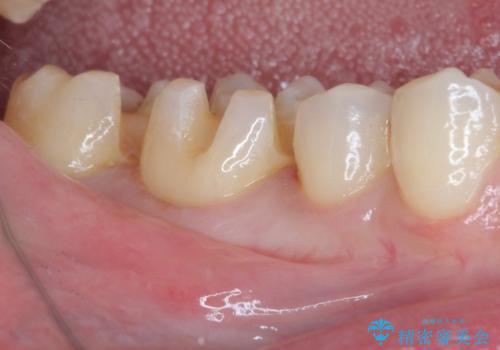

まず麻酔をして銀歯を外し、むし歯を除去し、形を整えて型取りします。

そして次の来院時、セラミックインレーを装着し、噛み合わせなどの調整を行います。

インレーを装着するときは、唾液や血液による接着力の低下を避けるためにラバーダム防湿を行いました。